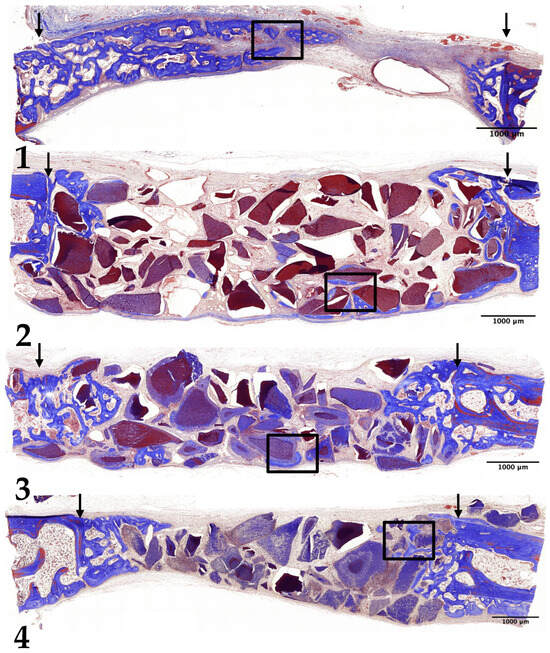

3.2. Two-Week Results

3.3. Four-Week Results